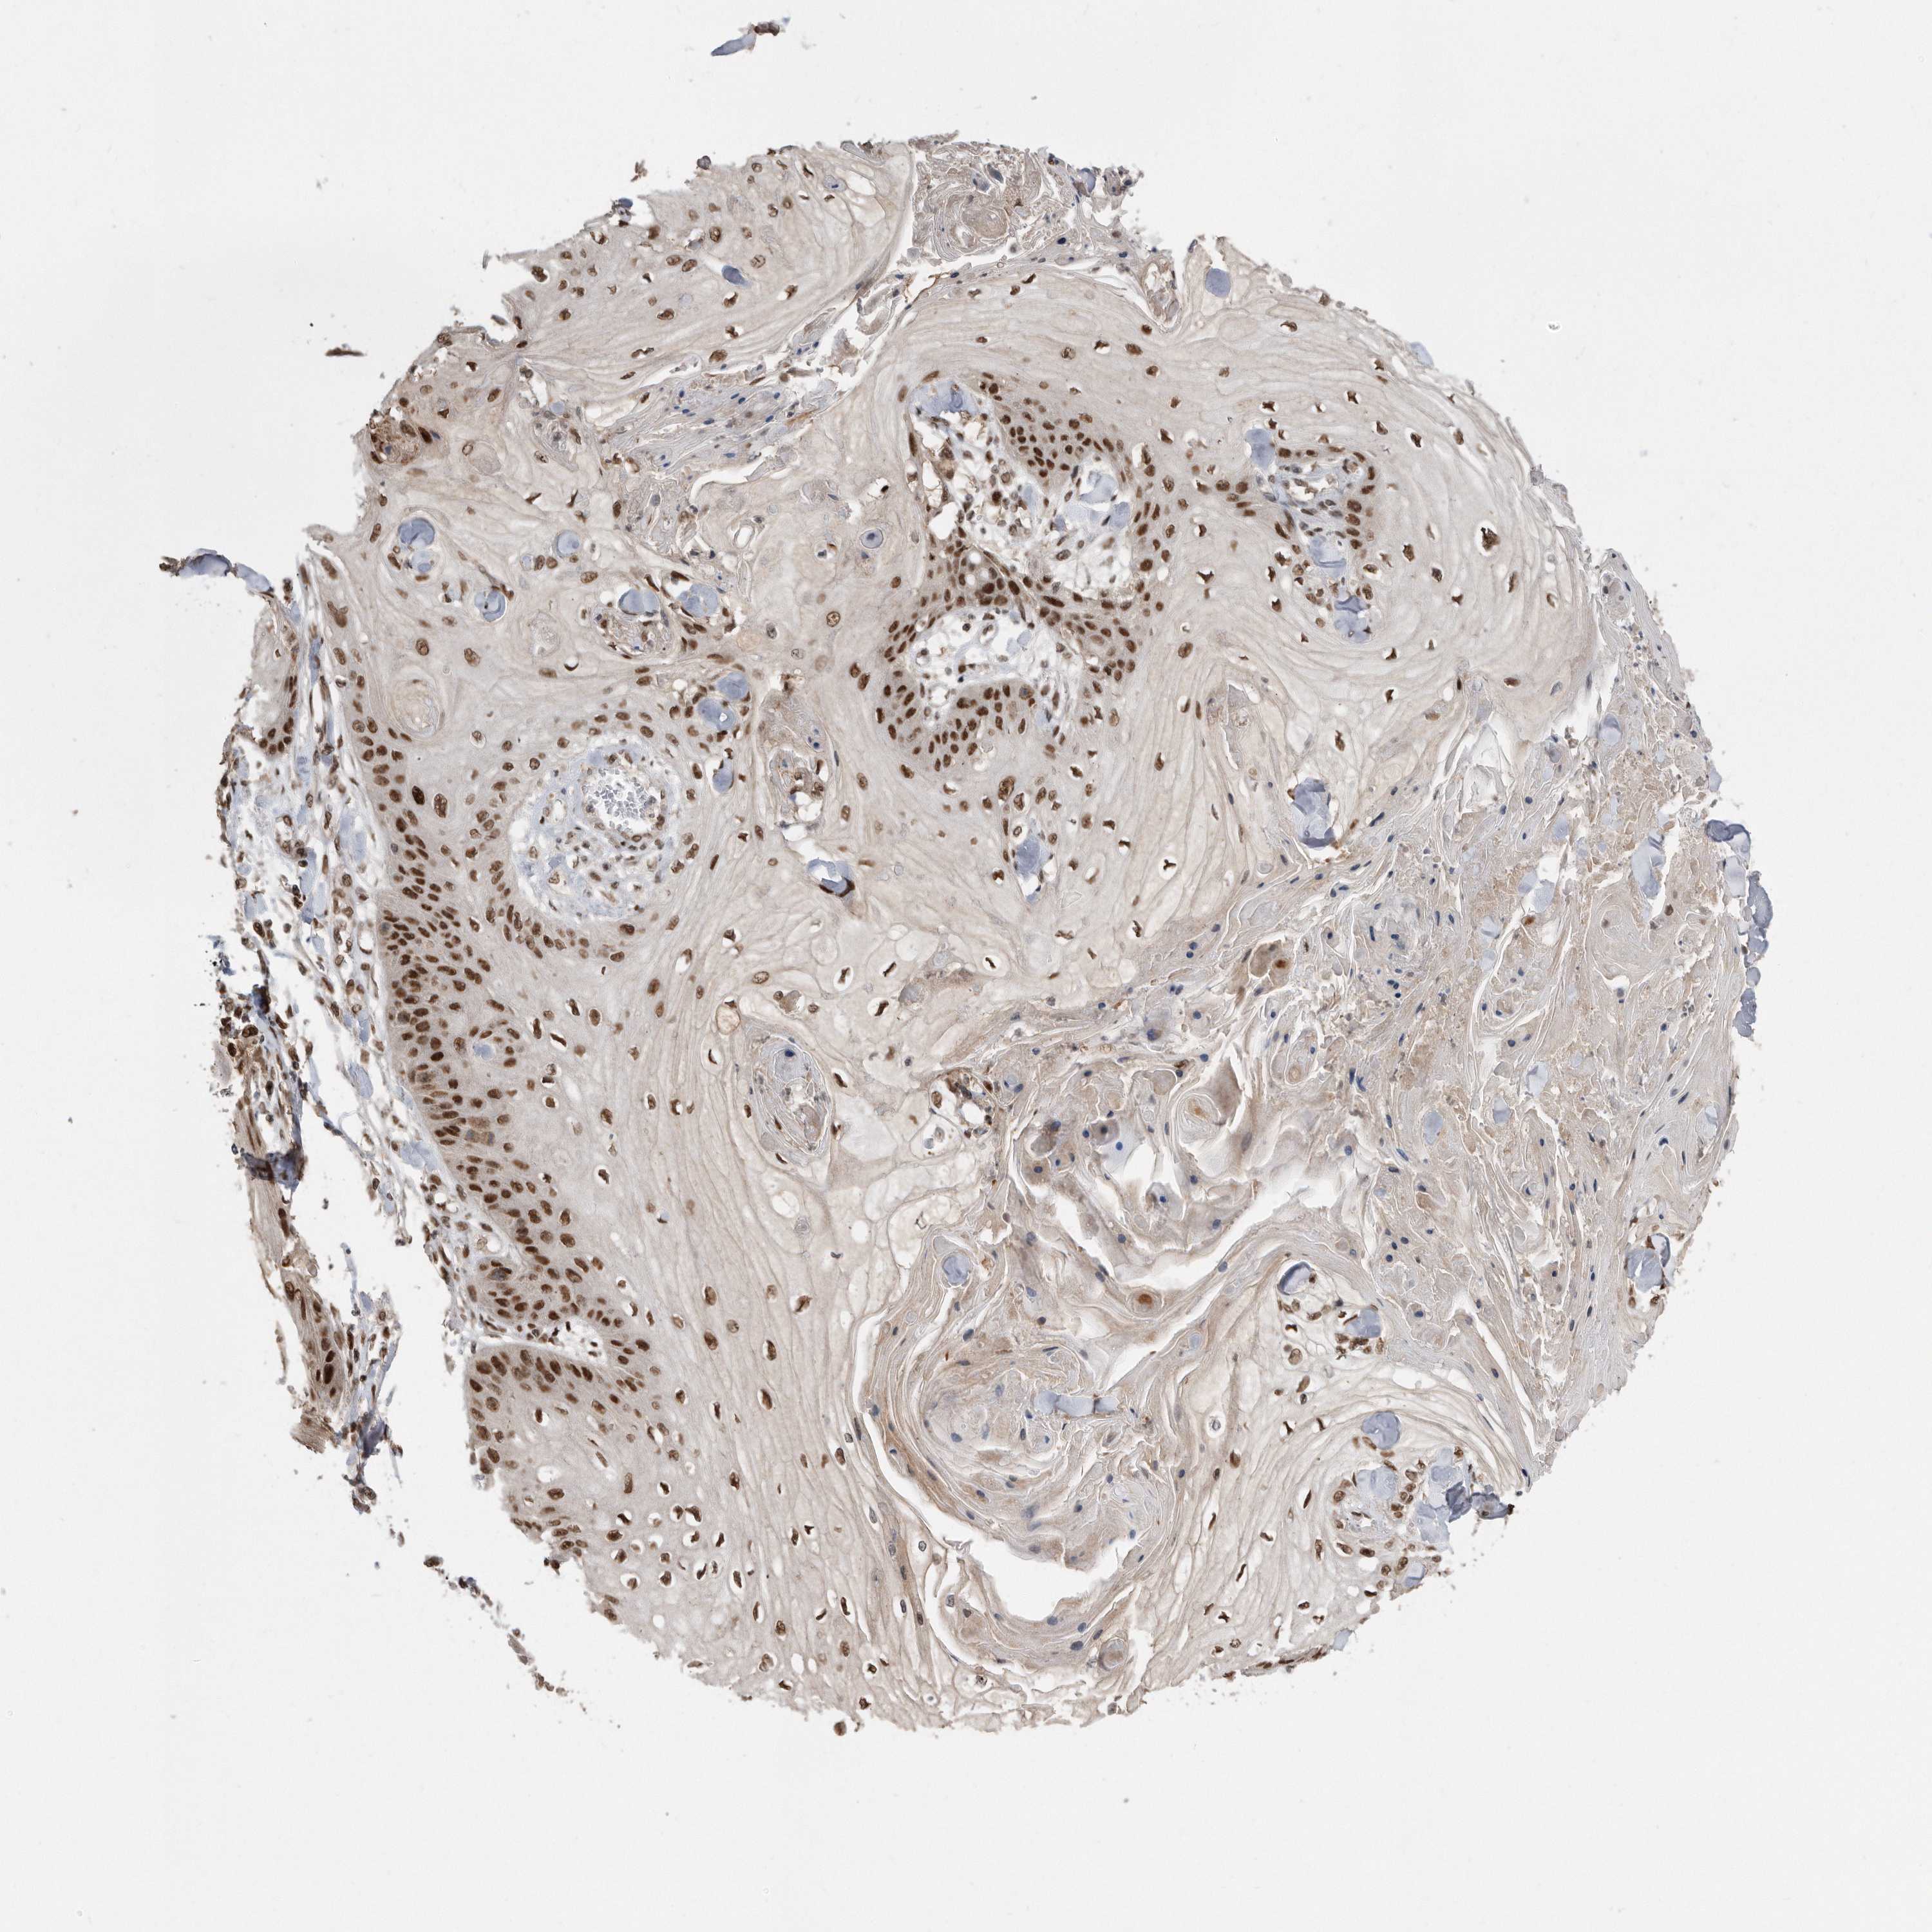

Basal cell and squamous cell cancer

SKIN CANCER - Protein expressioni

A mouse-over function shows sample information and annotation data. Click on an image to view it in a full screen mode. Samples can be filtered based on level of antibody staining by selecting one or several of the following categories: high, medium, low and not detected. The assay and annotation is described here.

Antibody stainingi

Antibody staining in the annotated cell types in the current human tissue is reported as not detected, low, medium, or high, based on conventional immunohistochemistry profiling in selected tissues. This score is based on the combination of the staining intensity and fraction of stained cells.

Each image is clickable and will lead to virtual microscopy that enables deeper exploration of all samples and also displays staining intensity scores, fraction scores and subcellular localization as well as patient and tissue information for each sample.

Antibody CAB034925

Staining

High

Intensity

Strong

Quantity

>75%

Location

Nuclear

Basal cell carcinoma